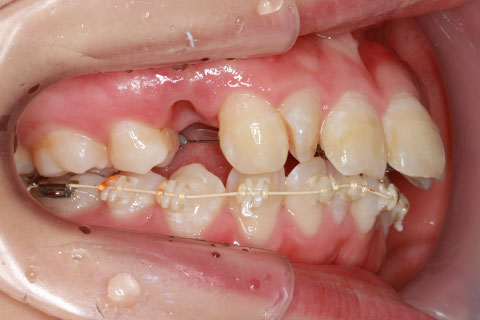

フルリンガル矯正1(上下の歯を舌側矯正で治療)

治療前

治療中

治療後

- 年齢・性別

- 33歳女性

- 治療期間

- 2年0ヶ月

- 抜歯

- 上顎4番抜歯。下顎5番欠損。

- 治療費

- 120万円(税込み)

- 備考

- フルリンガル矯正

- 治療内容

- 上顎前歯の叢生改善および下顎前歯の空隙閉鎖

- 施術の副作用(リスク)

- 装置が裏側について、目視ができないため、しっかりとブラッシングができているかどうかわかりにくい。